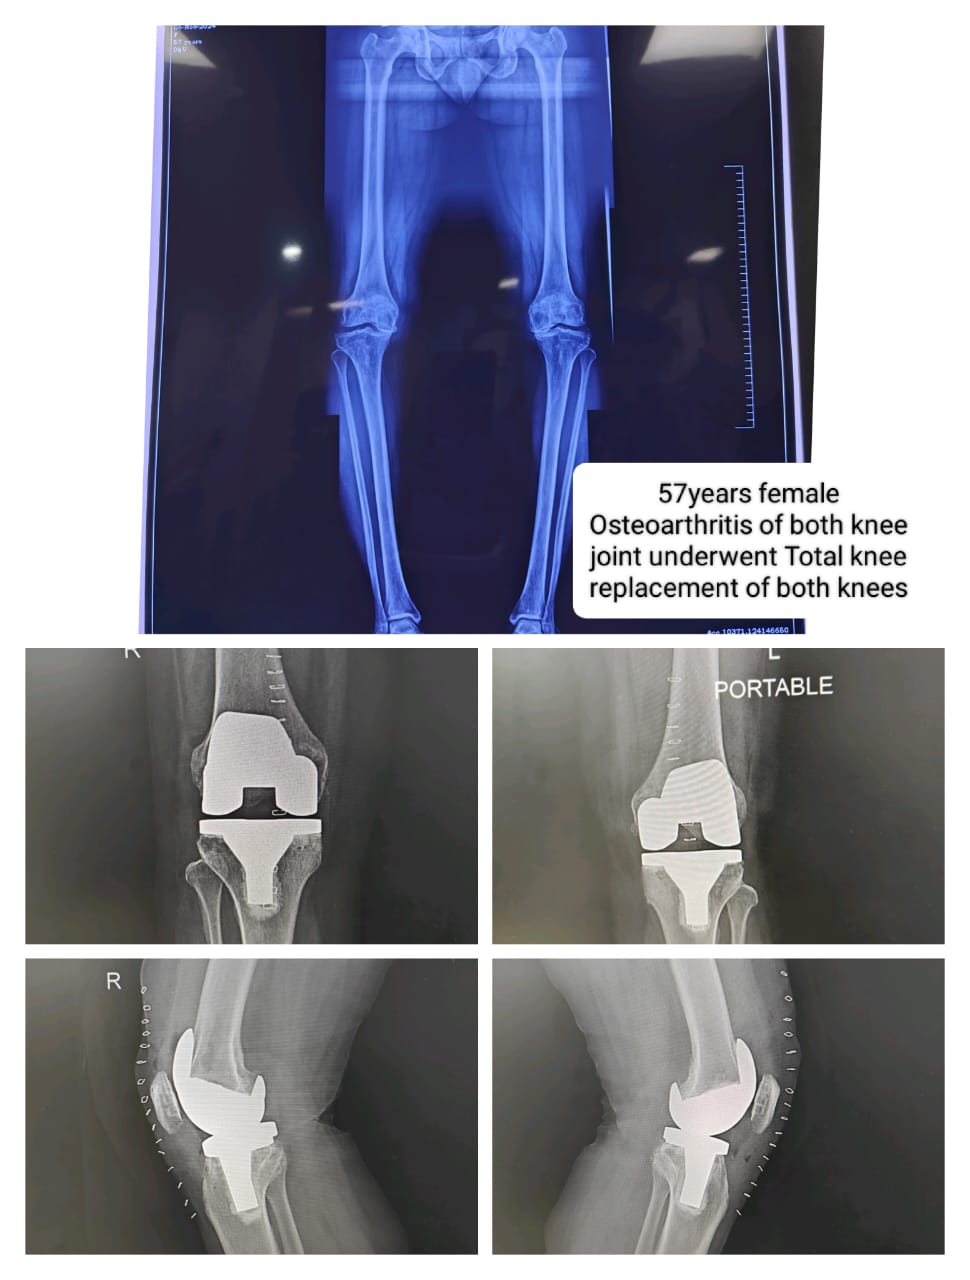

Case study